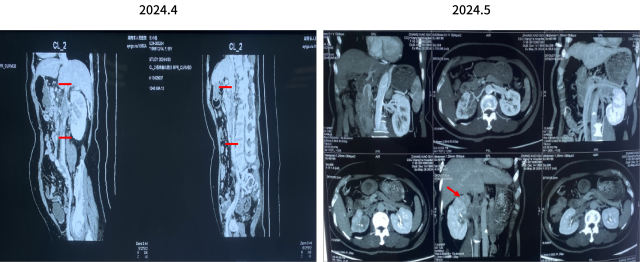

CT 肾脏平扫增强三维+肾血管成像 CTA+CTV,CT 肺部平扫+肺动脉成像 CTA

1.右肾上极稍低密度肿块灶及肾盂、输尿管上段壁明显增厚:考虑恶性病变,伴右肾静脉-下腔静脉-左肾静脉起始部癌栓形成可能性大,请结合临床。

2.右中肺外侧段肺动脉、左肺动脉干、左上下肺动脉多发栓塞。

3.左肺上叶尖后段混杂磨玻璃结节,LU-RADS 4B类,建议多学科会诊。

4.支气管炎。双肺下叶胸膜下少许炎症。

5.甲状腺双侧叶强化减低灶,建议结合超声检查。

6.左侧肾上腺结合部、内侧肢局限性增粗,意义待定。

日期:2024.5.29

双靶治疗(2个月)

双靶治疗(4个月)

2024.6.12 行根治性肾切除+腔静脉瘤栓取出术